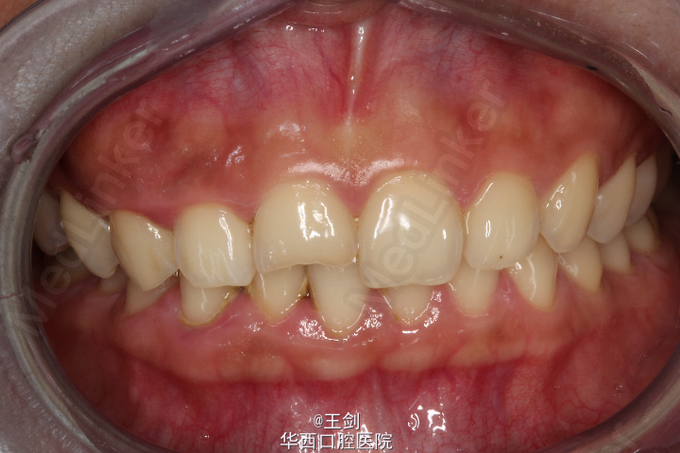

拟行CAD/CAM贴面修复11牙,当天备牙,当天戴牙

CAD/CAM 技术制作贴面可以达到高度密合,大大节省诊疗时间等优点